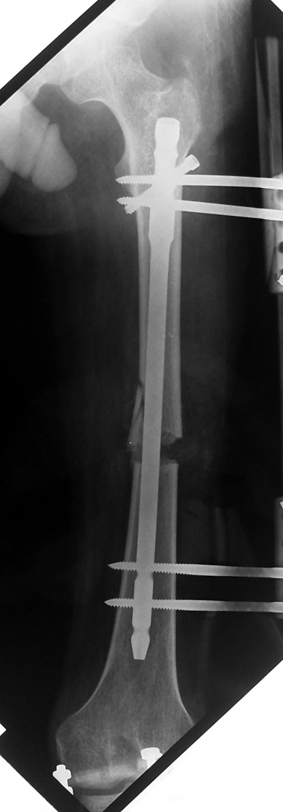

3. POSTTRAUMATIC LOWER LIMB SHORTNESS (MALUNION)

This type of shortness occurs after a fracture heals in a shortened position. Most cases are seen in adults and can be treated with one lengthening operation. Additional deformities can be corrected simultaneously. Most of these cases can be treated with lengthening over nail or just corrections and intramedullary nailing.